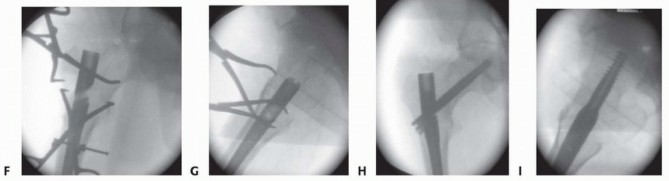

Fracture Reduction and Canal Preparation

A fracture reducer (TriGen) or similar curved cannulated device is inserted through the retained channel reamer to the fracture site and threaded through the fracture site into the distal fragment intramedullary canal, with manipulation in appropriate planes to align the fracture ( TECH FIG 4A). A long guide rod is inserted to the knee if a long nail is desired, confirming that the wire does not impinge on the anterior cortex distally. Preferably, the guide rod should be inserted to the old physeal scar and centered on AP and lateral Carm views ( TECH FIG 4B). The reducer is removed and the guidewire position is maintained with an obturator proximally. Length is checked with an appropriate ruler, allowing for fracture distraction and nail final position. The diaphyseal region is reamed up to 1 mm over the desired nail size (up to 2 mm for excessive anterior bows) ( TECH FIG 4C). The proximal expansion of the nail should have already been reamed with the entry portal reamer, but the surgeon should always confirm diameters. The channel reamer is removed and the selected nail is inserted ( TECH FIG 4D). For long trochanteric nails, it is helpful to rotate the nail 90 degrees anteriorly during the first half of the nail insertion to minimize hoop stresses in the proximal femur. After partial insertion, the nail is rotated to the anticipated anteversion required for femoral head fixation. The last 5 cm of the nail is inserted after releasing distraction sufficient for fracture apposition, maintaining correct rotational alignment. Most commercial guides use reference marks to align with the femoral head on the lateral C-arm view. These same guides may be used for C-arm verification of correct depth of insertion to allow optimal femoral head fixation.

The long guide rod is removed to proceed with interlocking.

TECH FIG 4 • A. Insertion of reducer through channel reamer, lateral radiographic view. B. Reducer directed guide rod centered on lateral radiograph, avoiding anterior distal cortex. C. Diaphyseal reaming through channel reamer. D. Nail insertion. For trochanteric nail, the surgeon matches the curve of the nail with the proximal femur during initial insertion to minimize hoop stress at entry portal. The nail is rotated into correct position after 30% to 50% insertion. 4. ## Single-Screw or Single-Device Designs (Gamma, Stryker; IMHS, Smith & Nephew; TFN, DePuy Synthes) The center-center wire is inserted to within 5 mm of subchondral bone. Fracture reduction is confirmed and the length to lateral cortex is measured.